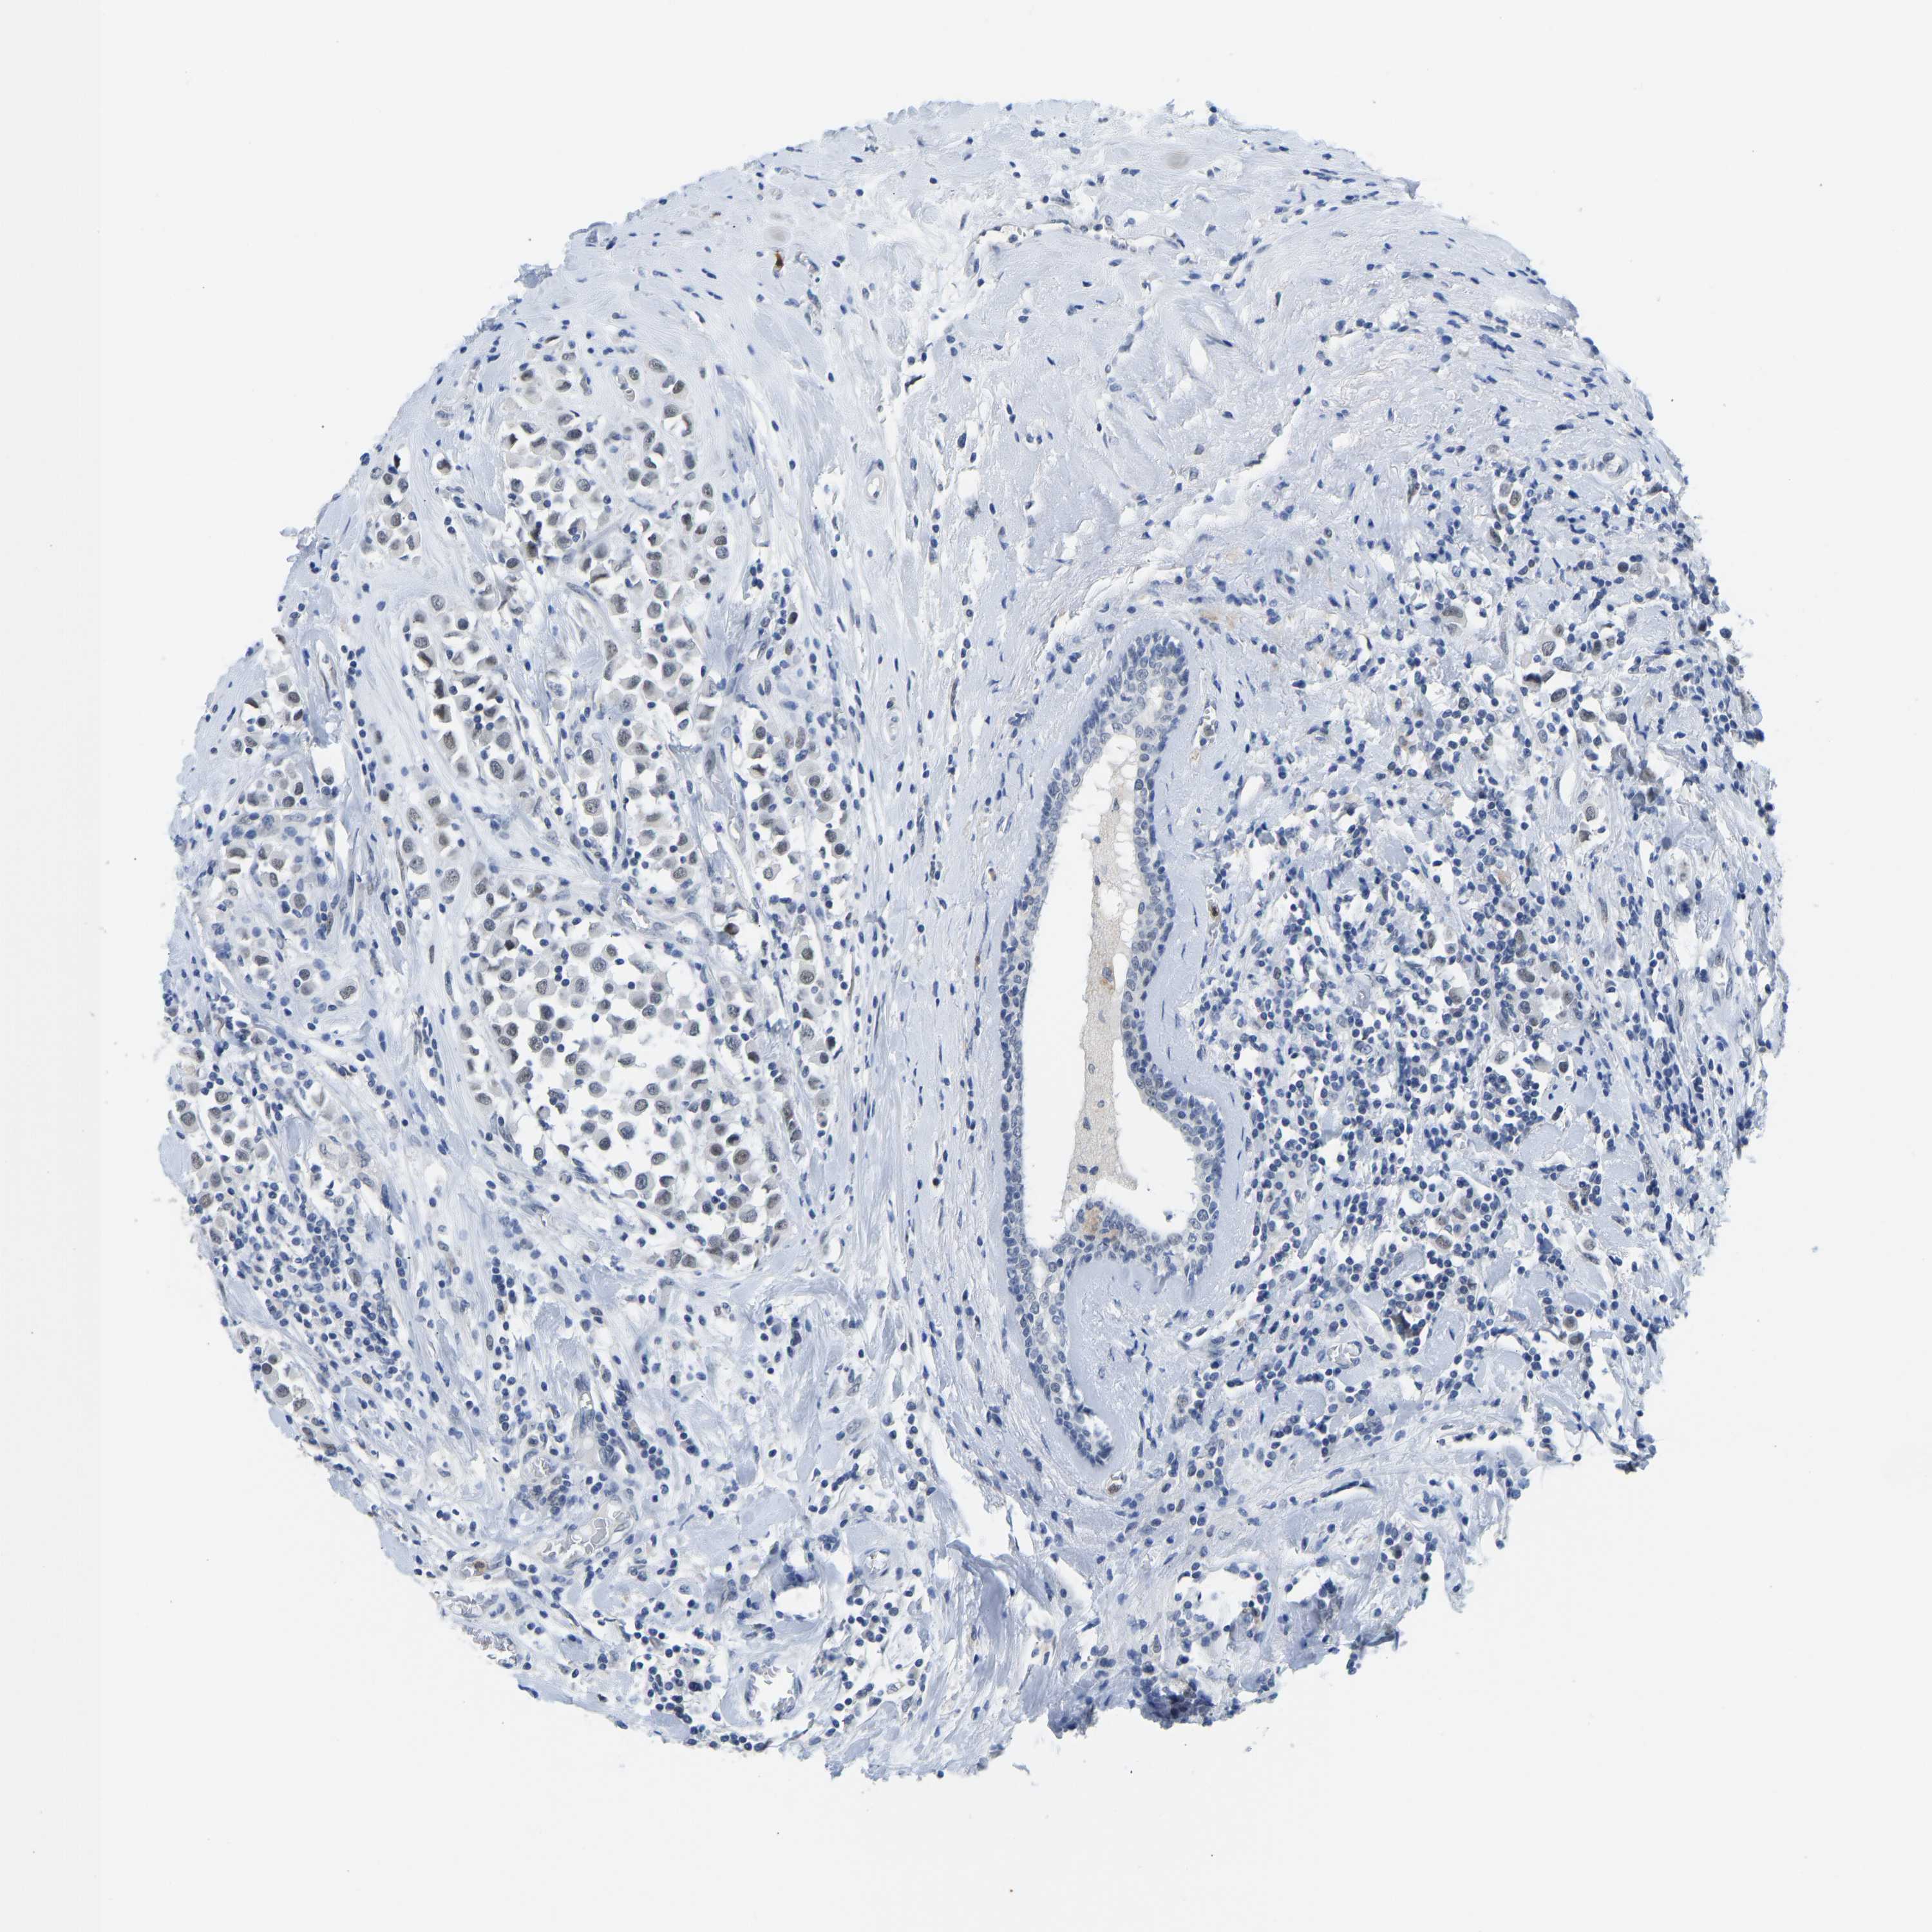

CANCER BREAST CANCER Show tissue menu

BRCA TCGA BRCA VALIDATION PROTEIN EXPRESSION